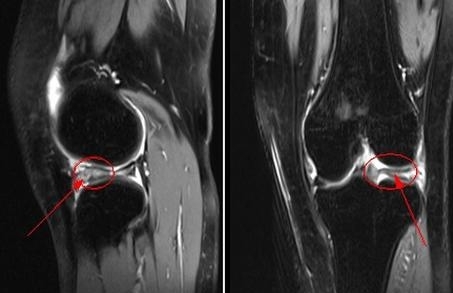

膝关节痛是本病患者就医常见的主诉。其早期症状为上下楼梯时的疼痛,尤其是下楼时为甚,呈单侧或双侧交替出现,出现膝关节肿大,多因骨性肥大造成,也可关节腔积液。